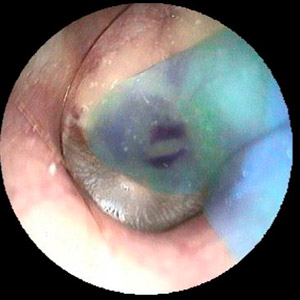

Loch im Trommelfell nach Schienung mit Silikon

Trommelfell nach Rekonstruktion mit Muskelhaut